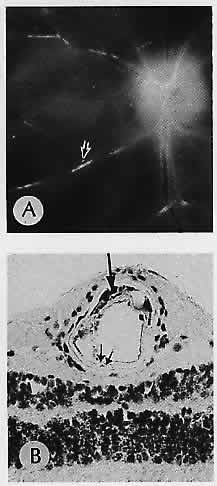

Fig. 5. Atherosclerosis. A. Gross appearance Of the fundus of an eye removed postmortem. Arrow indicates plaque in the inferonasal arteriole, seen microscopically in (B). B. Frozen section stained with oil red-O shows lipid deposits (arrow) in atheromatous plaque. Note the fatty infiltration in the muscular wall at the edge of the artifactitious cleft (double arrow). (A, macroscopic; B, oil red-O, ×200)

Cholesterol emboli are commonly seen in patients who have ulcerated atheromatous plaques of the carotid arteries. Often, however, these emboll do not occlude the vessel because their shape does not readily conform to the shape of the vessel. These are seen clinically as Hollenhorst plaques and appear as bright shiny yellow emboli within the vessels (Fig. 6).30

Fig. 6. Emboli. A. Retinal vessel on the left (v) is occluded by an osmophilic fat globule. A smaller fat globule (arrow) is seen in the vessel on the right. The retinal arteriole fat emboli followed closed-chest cardiac massage. B. Cholesterol embolus in a retinal artery (arrow). Inset 1. Higher magnification of the embolus. Inset 2. Clinical appearance of a cholesterol embolus (arrow) in the same eye prior to enucleation. Multiple cholesterol emboli (Hollenhorst plaques) were present in the fundus of a 67-year-old man with carotid artery stenosis. (A, PD ×300; B, H&E ×40; inset 1, H&E × 101; inset 2, clinical)